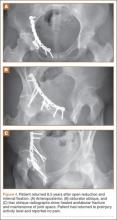

Thirty-seven patients underwent acetabular fracture ORIF. Immediate postoperative radiographs showed 30 anatomical reductions and 7 imperfect reductions. One patient had surgical secondary congruence and developed AVN of the hip. We could not identify an association between the quality of the reduction and the outcome with respect to pain or return to activity. However, no patient had a poor reduction. An illustrative case is presented in Figures 1 to 4.

Other complications included 1 case of deep infection of the surgical wound. This infection presented 4 months after surgery and was treated with débridement, hardware removal, and a 3-month course of antibiotics. Two patients who sustained hip dislocations at time of injury developed AVN of the femoral head. Both developed osteoarthritis, and 1 underwent hip fusion. Eight patients developed heterotopic ossification on the side of the acetabular fracture; 4 of them underwent surgical excision. Four patients required a separate operation for hardware removal. Four patients with triradiate cartilage involvement went on to premature closure. No patient had any leg-length discrepancy or dysplasia at time of follow-up.